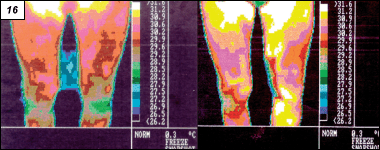

Obr. 14. Meranie na výmenníku tepla V niekoľko posledných rokoch bol vyvinutý i špeciálny programový produkt určený pre stavebné aplikácie, ktorý umožňuje pri meraní veľkých objektov poskladať jednotlivé termogramy do jedného obrazu a výsledný obraz vyhodnotiť ako jeden termogram. 2.4 Teplovodné a parovodné systémy Na obr. 14, 15 sú fotografie a tepelné obrazy, na ktorých sú zrejmé úniky v teplovodných rozvodoch a na zariadeniach (výmenník tepla, kotol), ktoré sú ich súčasťou. Obr. 19. Meranie na spaľovacom motore 2.5 Medicína 2.6 Ekológia Obr. 20. Rozloženie teploty na asfaltovom chodníku Termovízny systém býva zabudovaný do vrtulníku alebo lietadla a používa sa na snímanie a následné vyhodnocovanie tepelných obrazov vo vybraných lokalitách (teda na meranie v hromadných zástavbách), kde pri meraní v určitej dobe možno získať poznatky o mikroklímach, pričom bude k dispozícii informácia o naakumulovaní a odovzdávaní tepelnej energie rôznymi objektmi, ale i časťami terénu. Vhodnými úpravami následne možno regulovať tepelnú záťaž (napr. vysádzaním porastu) a z vyhodnotenia hodnôt nameraných na zemskom povrchu napr. je možné dostať informácie o stave porastov a pod. Ďalej možno s využitím tejto metódy diagnostikovať, či sa vo vodných nádržiach nevyskytujú miesta so zvýšenou teplotou v dôsledku nedostatočného prúdenia vody, ktoré sú nebezpečné pre živočíchy, rastliny a pod. 2.7 Priemysel Obr. 21. Sledovanie priestoru uhoľnej skládky Termovízne meranie je svojou fyzikálnou podstatou veľmi presné. Umožňuje dokonale lokalizovať merané miesto, nedochádza pri ňom k zavedeniu systémovej chyby vplyvom tepelnej kapacity kontaktného teplomeru alebo zmeny teploty z dôvodu časovej doby merania, urýchľuje snímanie teploty a tak sa eliminuje chyba spôsobená tepelnou vodivosťou materiálu a prostredia. Termovízne systémy vyrábané v súčasnej dobe sa vyznačujú unikátnymi vlastnosťami medzi podobnými prístrojmi: dovoľujú zobraziť teplotu plameňa a taktiež merať teplotu cez niektoré transparentné materiály (napr. sklená tabuľa, priehľadný film a pod.). Na obr. 17 až obr. 19 sú uvedené niektoré príklady využitia termovízie v priemysle. Termovízne systémy sa využívajú aj na sledovanie takých objektov, kde je dôležitá ochrana pred vznikom požiaru napr. na skladovacích materiáloch (skládky uhlia – obr. 21, pneumatík, technológie v cementárni, na reguláciu povrchových teplôt rôznych materiálov (obr. 20), prístrojov (obr. 22) a pod.) s rizikom ich vznietenia. Obr. 22. Termogram žehličky ETA 2.8 Výskum a vývoj